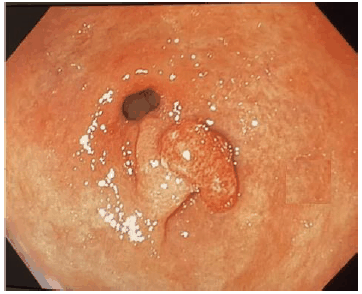

Analise a imagem a seguir.

Enunciado 3137034-1

De acordo com a classificação de Paris, a imagem acima é corretamente classificada como